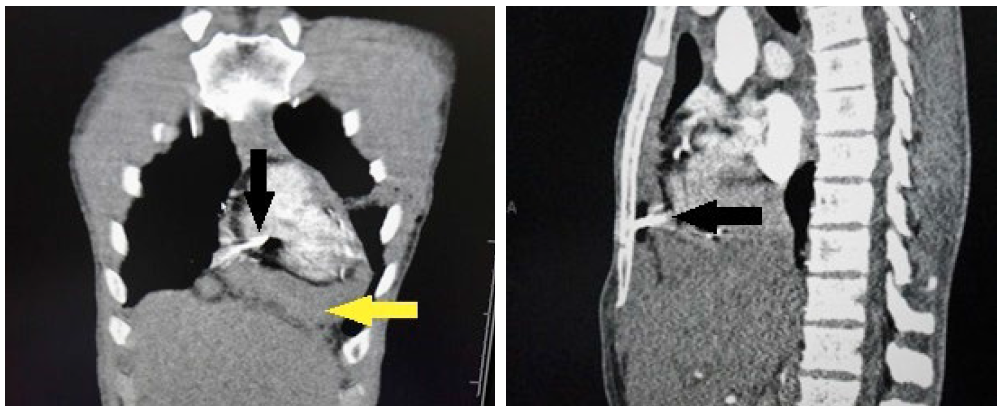

图2:CT显示钉子已经穿透心包,黄色箭头为心包积液。

图3:胸骨后的钉子尖端穿透心包。前纵膈可见血肿。